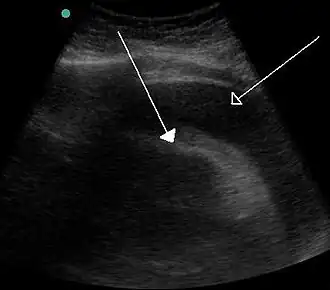

Chez un patient en état de choc, le recours à l'échographie peut permettre de diagnostiquer un épanchement péricardique[10].

Un épanchement « asymptomatique » découvert à l'échographie nécessite une analyse rigoureuse des images bidimensionnelles et des variations respiratoires des flux doppler afin d'apprécier le risque de tamponnade[10].

La tamponnade peut souvent être diagnostiquée par radiographie. L'échocardiographie, qui est le test diagnostique majeur, montre souvent un péricarde élargi ou des ventricules affaissés. Une tamponnade cardiaque importante se manifestera par un cœur élargi de forme globulaire sur la radiographie pulmonaire. Pendant l'inspiration, la pression négative dans la cavité thoracique entraînera une augmentation de la pression dans le ventricule droit. Cette pression accrue dans le ventricule droit provoquera un renflement du septum interventriculaire vers le ventricule gauche, entraînant une diminution du remplissage du ventricule gauche. Dans le même temps, le volume du ventricule droit est nettement diminué et parfois il peut s'effondrer[14].